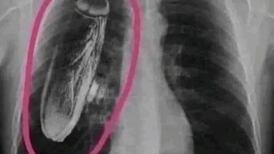

Imagen difundida en redes no corresponde a la actividad realizada frente a la Asamblea Legislativa